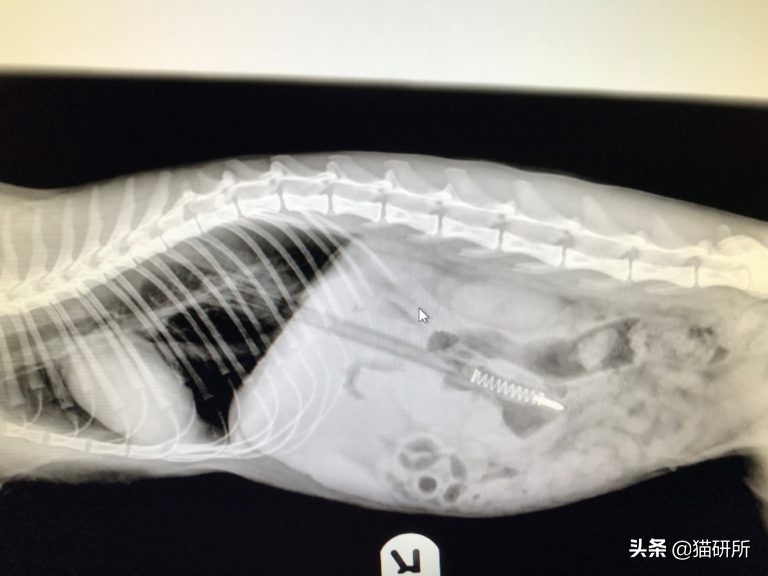

甚至还有一些“勇士”,吞下的东西并不那么常规,也并不“小”……

这只猫咪吞下了一只笔……图自:iheartcats